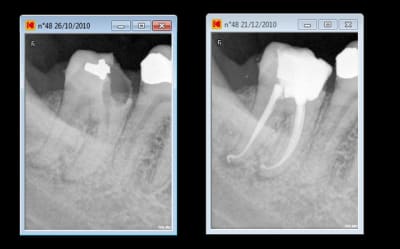

et pour le fun comme je m'ennuie et que les fouillanouchets sont point à la maison ct'ap je bosse et me fait plaisir chti't tof

Chances l7d25t - Eugenol